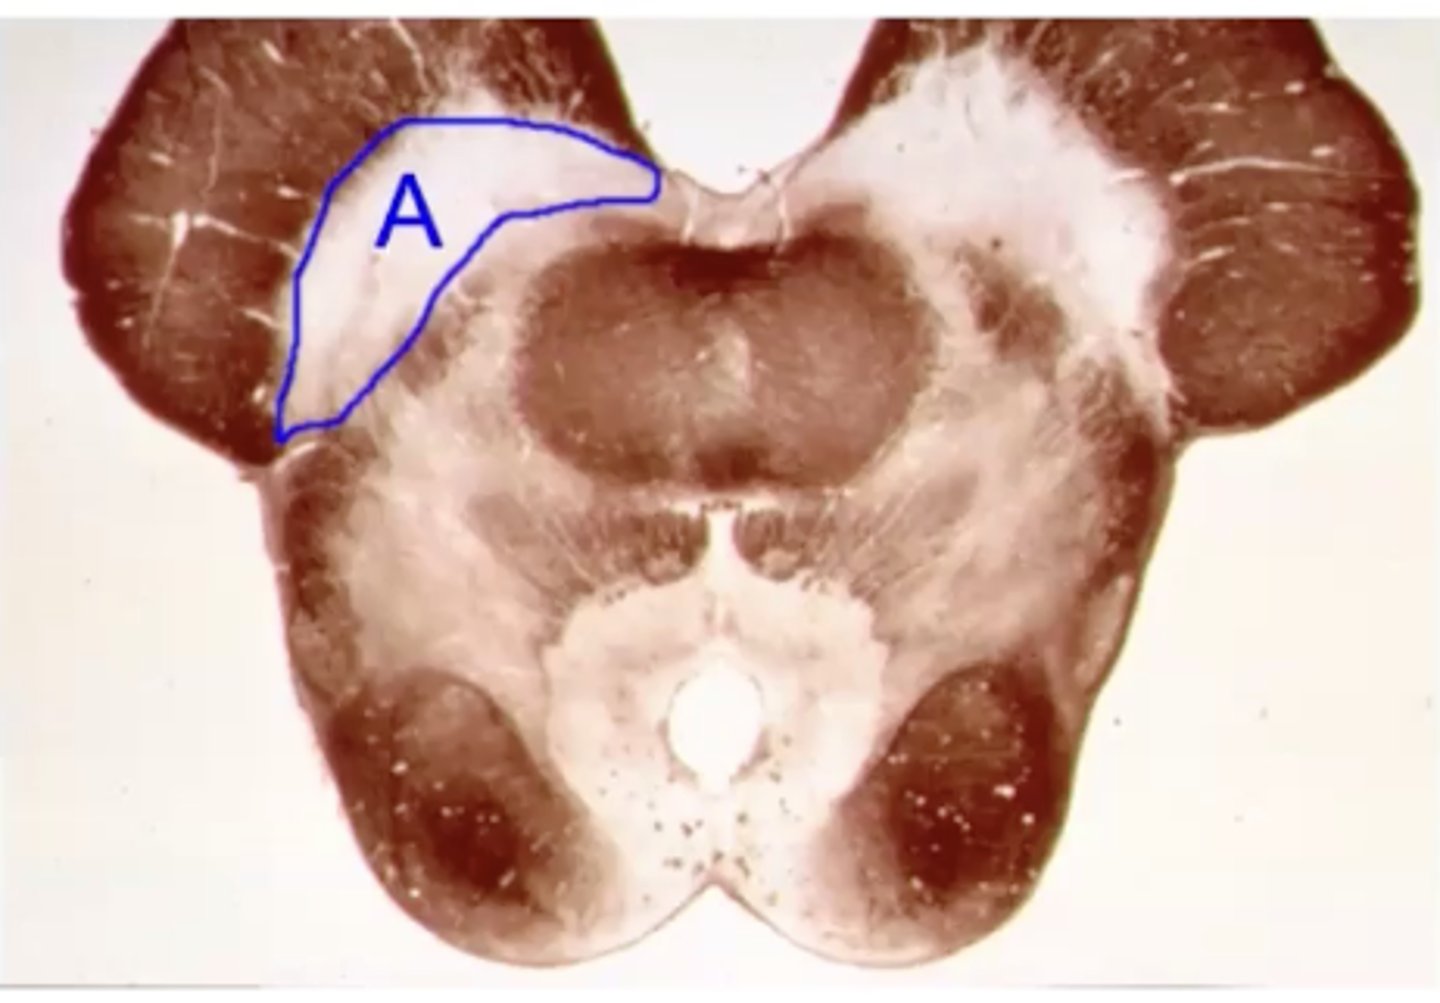

parkinsons

name the clinical condition when A is lesioned